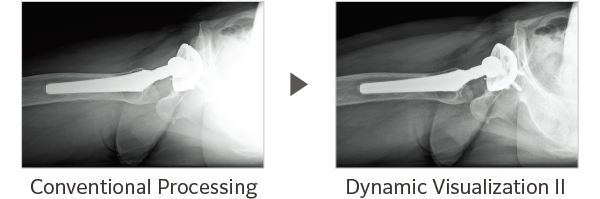

Dynamic Visualization II

Optimizes image quality using latest Exposure Data Recognizer

Advanced recognition algorithms using automatic  calculations of estimated 3D image data, identify the body part required and adjusts contrast, density and enhancement for optimised image display. (Option)

Comparison of Dynamic Visualization II vs. conventional processing images (Hip Joint)